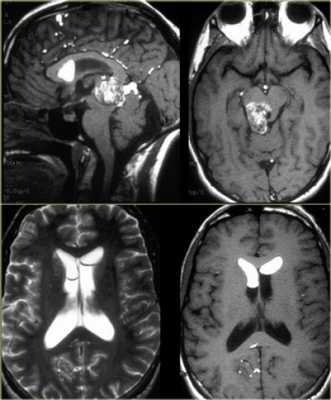

Пинеоцитома - доброкачественная опухоль, возникающая из ткани шишковидной железы, имеющая четкие контуры (рис.724, 725).

Пинеоцитома - доброкачественная опухоль, происходящая из паренхимы corpus pineale, хорошо ограниченное, инкапсулированное, медленно растущее, неинвазивное поражение. Опухоль может содержать кальцинаты по периферии [137]. Размеры образования могут быть различны, но это не связано с атипией опухоли. На КТ пинеоцитомы были описаны как → или слегка ↑, на МРТ это солидная фракция описывается, как ↓T1 и →Т2 [137].

Объёмное образование шишковидной железы, представленное мягкотканным образованием с наличием капсулы (стрелки на рис.729, 730). Пинеоцитома может иметь кисты (головка стрелки на рис.728).

Контрастное усиление

На КТ и МРТ солидные компоненты интенсивно накапливают контраст [34,43,49,53,130].

Интенсивное контрастирование солидных участков пинеоцитомы (стрелки на рис.731-733).